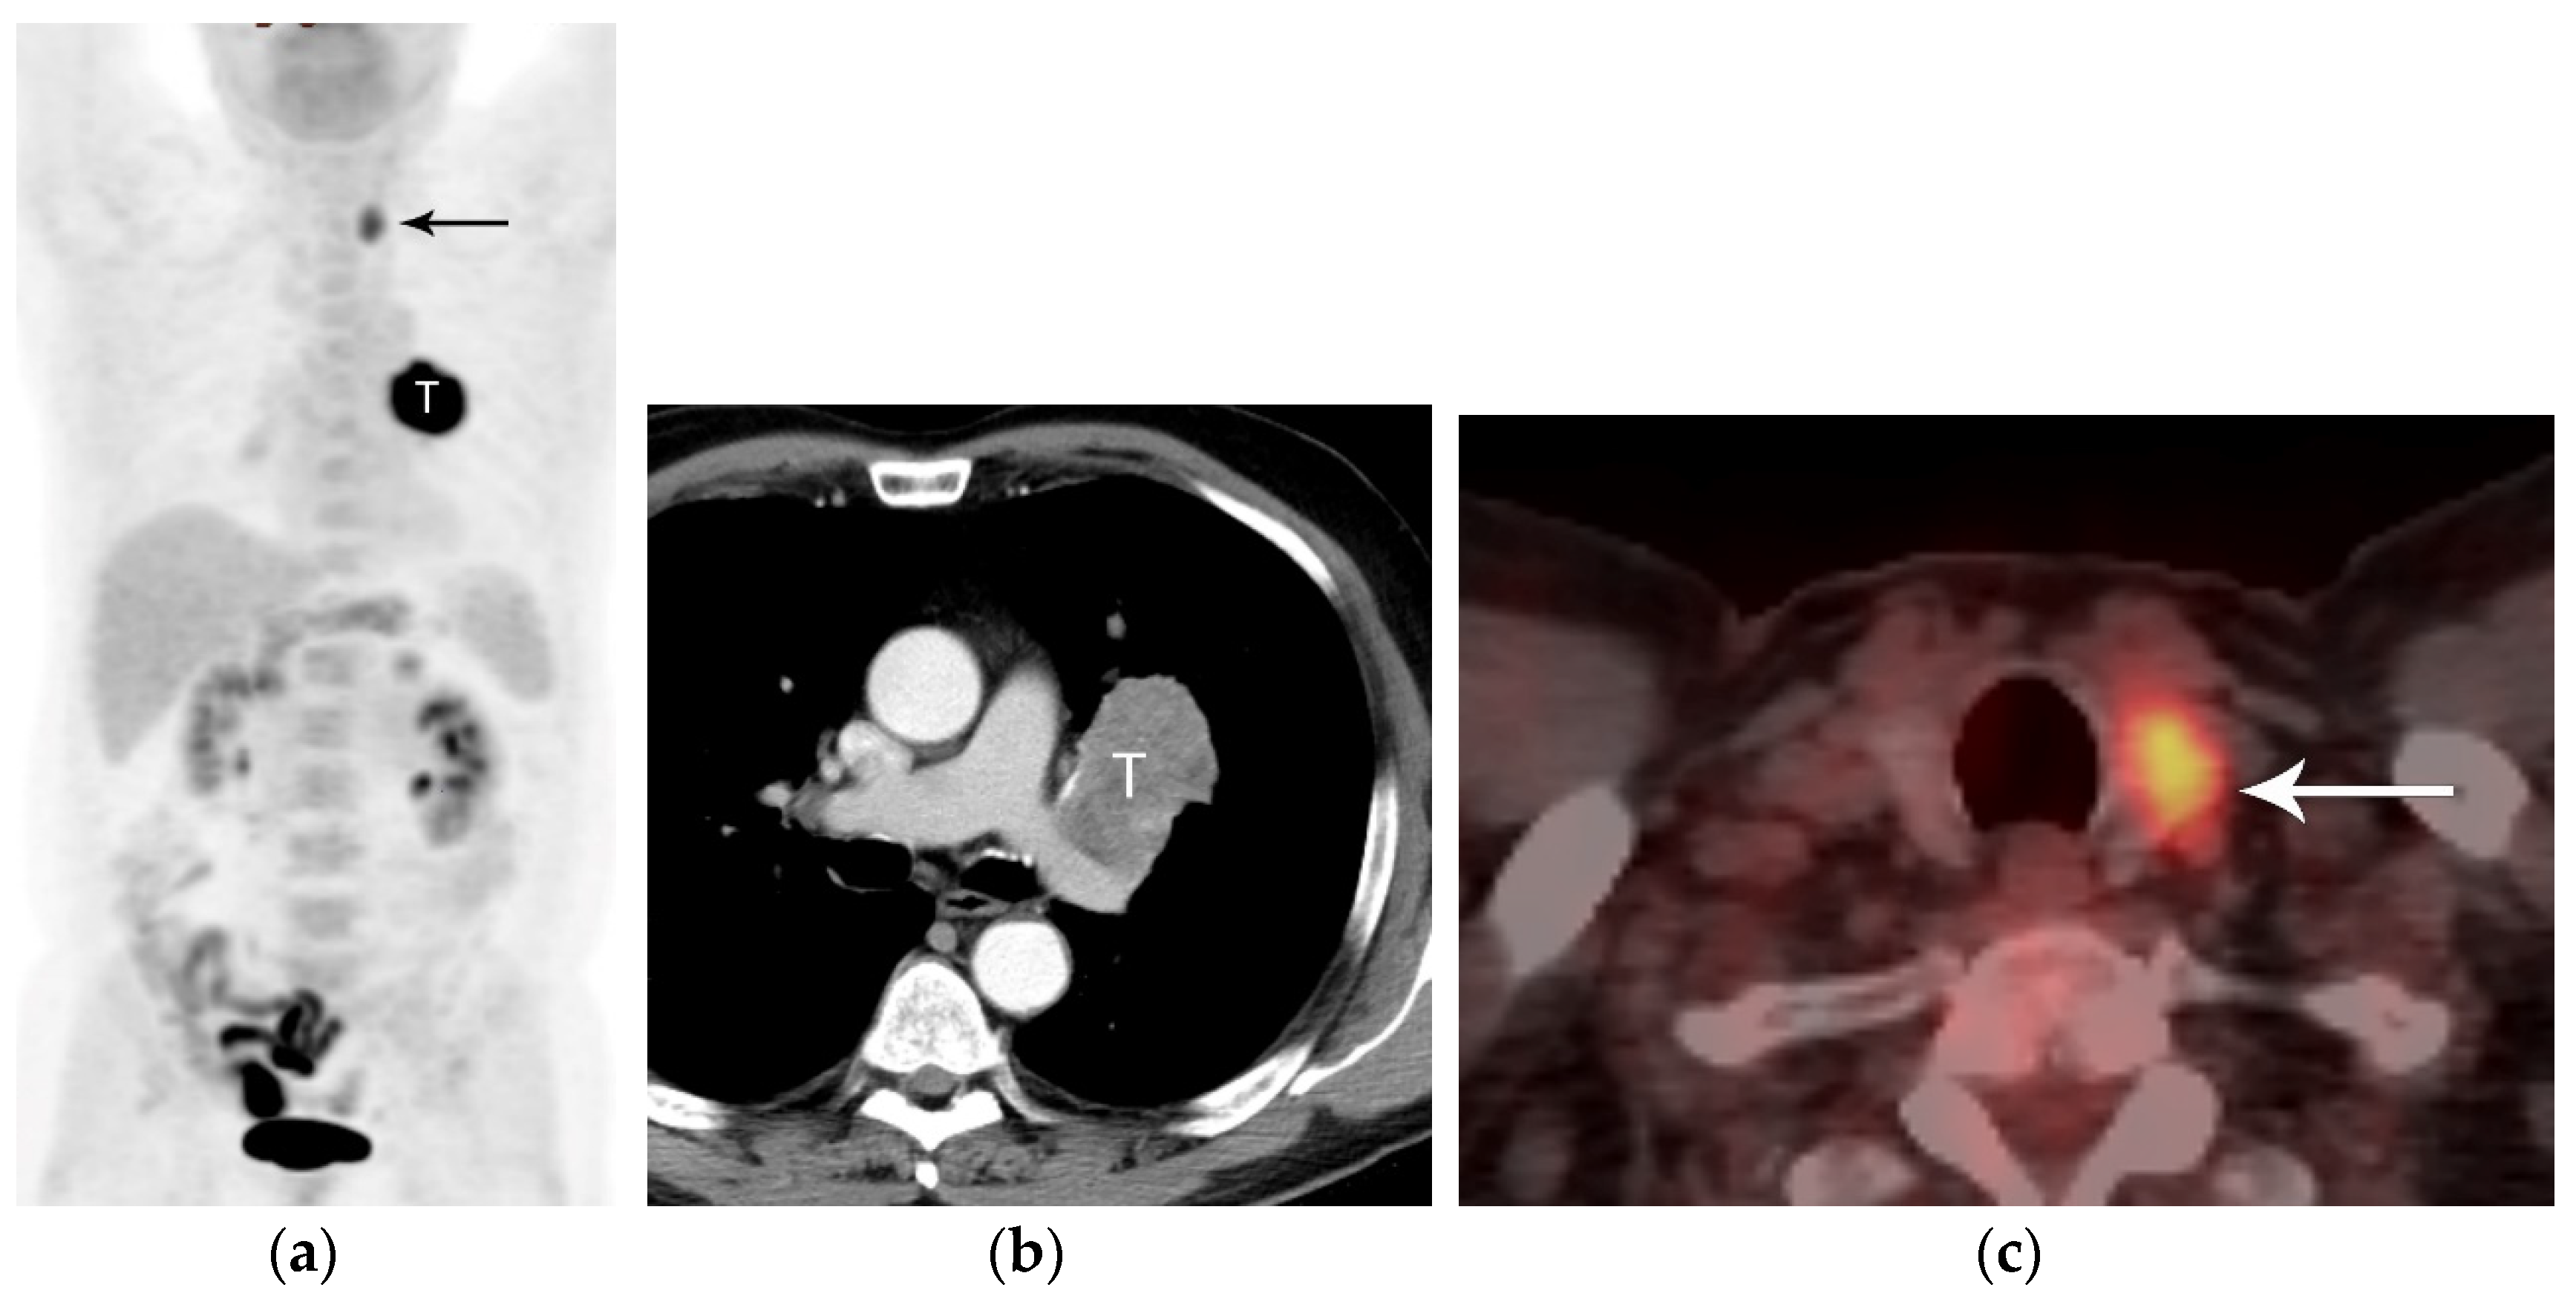

3. N Classification

5. Resectability

6. PET/CT for Lung Cancer